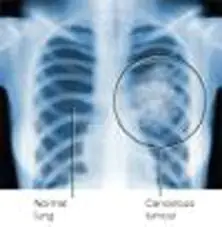

Mesothelioma Xray